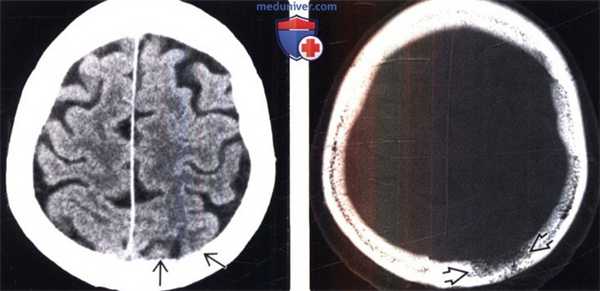

(Слева) Метастатическое поражение черепа может быть трудно увидеть на рутинных бесконтрастных КТ -изображениях с использованием мягкотканного алгоритма реконструкции. Бесконтрастная КТ, аксиальный срез: малозаметная эрозия внутренней компактной пластинки свода черепа.

(Справа) Бесконтрастная КТ, костный алгоритм реконструкции, аксиальный срез: у этой же пациентки отчетливо визуализируется эрозивное деструктивное поражение. В данном случае это поражение представляло собой первое проявление метастатического рака молочной железы.